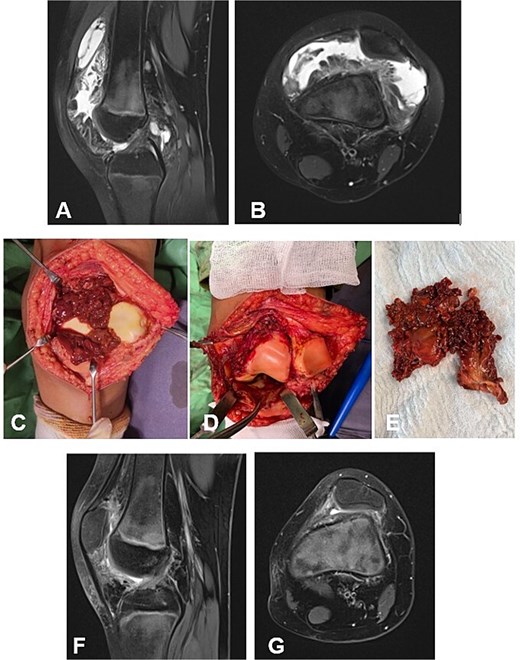

Case 1. (A and B) Preoperative T1 sagittal and axial MRI sequences with PD FS. (C and F) Macroscopic appearance of the pathological synovium before and after its excision. (D and E) The knee joint following synovectomy, demonstrating intact menisci and cruciate ligaments. Chondral lesions correspond to Outerbridge grade IV. (G and H) Postoperative 24 m. Sag and Ax MRI PD FS. No evidence of recurrence of the resected neoplasm was detected. Residual TGCT involvement persists within the lateral posterior femoral recesses. PD FS, proton density weighting with fat suppression; TSE, turbo spin echo.

Case 1

A 4-year-and-5-month-old child presented with a history of chronic synovitis of the right knee joint persisting for more than 2 years. Progressive limitation of motion was observed—a 15° flexion contracture, and maximum flexion limited to 75°. Magnetic resonance imaging (MRI) was concordant with the intraoperative findings, demonstrating diffuse involvement of both anterior and posterior recesses of the knee joint (Fig. 2A–C). A subtotal anterolateral synovectomy was performed. Intraoperatively, chondral defects corresponding to Outerbridge grade IV were identified (Fig. 2C–E). At 2-year follow-up, a substantial improvement in the range of motion was achieved (Table 1). Follow-up MRI demonstrated no evidence of local recurrence in the previously resected area of the neoplasm (Fig. 2G–H). A secondary synovectomy is planned to address residual synovial involvement within the posterior lateral femoral recess.